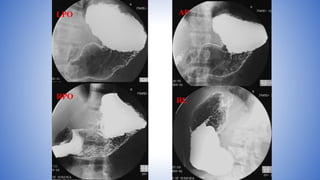

• Take four DC spot images of the entire stomach using the largest

FOV in the following sequence:

• LPO position

• AP (supine)

• RPO

• Right lateral (Wait until duodenal C-loop is sufficiently filled with barium;

otherwise, take this film at end of study.)

LPO AP

RPO

RL